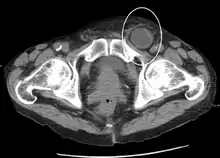

Medical imaging

A physician may diagnose an inguinal hernia, as well as the type, from medical history and physical examination.[20] For confirmation or in uncertain cases, medical ultrasonography is the first choice of imaging, because it can both detect the hernia and evaluate its changes with for example pressure, standing and Valsalva maneuver.[21]

When assessed by ultrasound or cross sectional imaging with CT or MRI, the major differential in diagnosing indirect inguinal hernias is differentiation from spermatic cord lipomas, as both can contain only fat and extend along the inguinal canal into the scrotum.[22]

On axial CT, lipomas originate posterolateral to the cord, and are located inside the cremaster muscle, while inguinal hernias lie anteromedial to the cord and are not intramuscular. Large lipomas may appear nearly indistinguishable as the fat engulfs anatomic boundaries, but they do not change position with coughing or straining.[22]